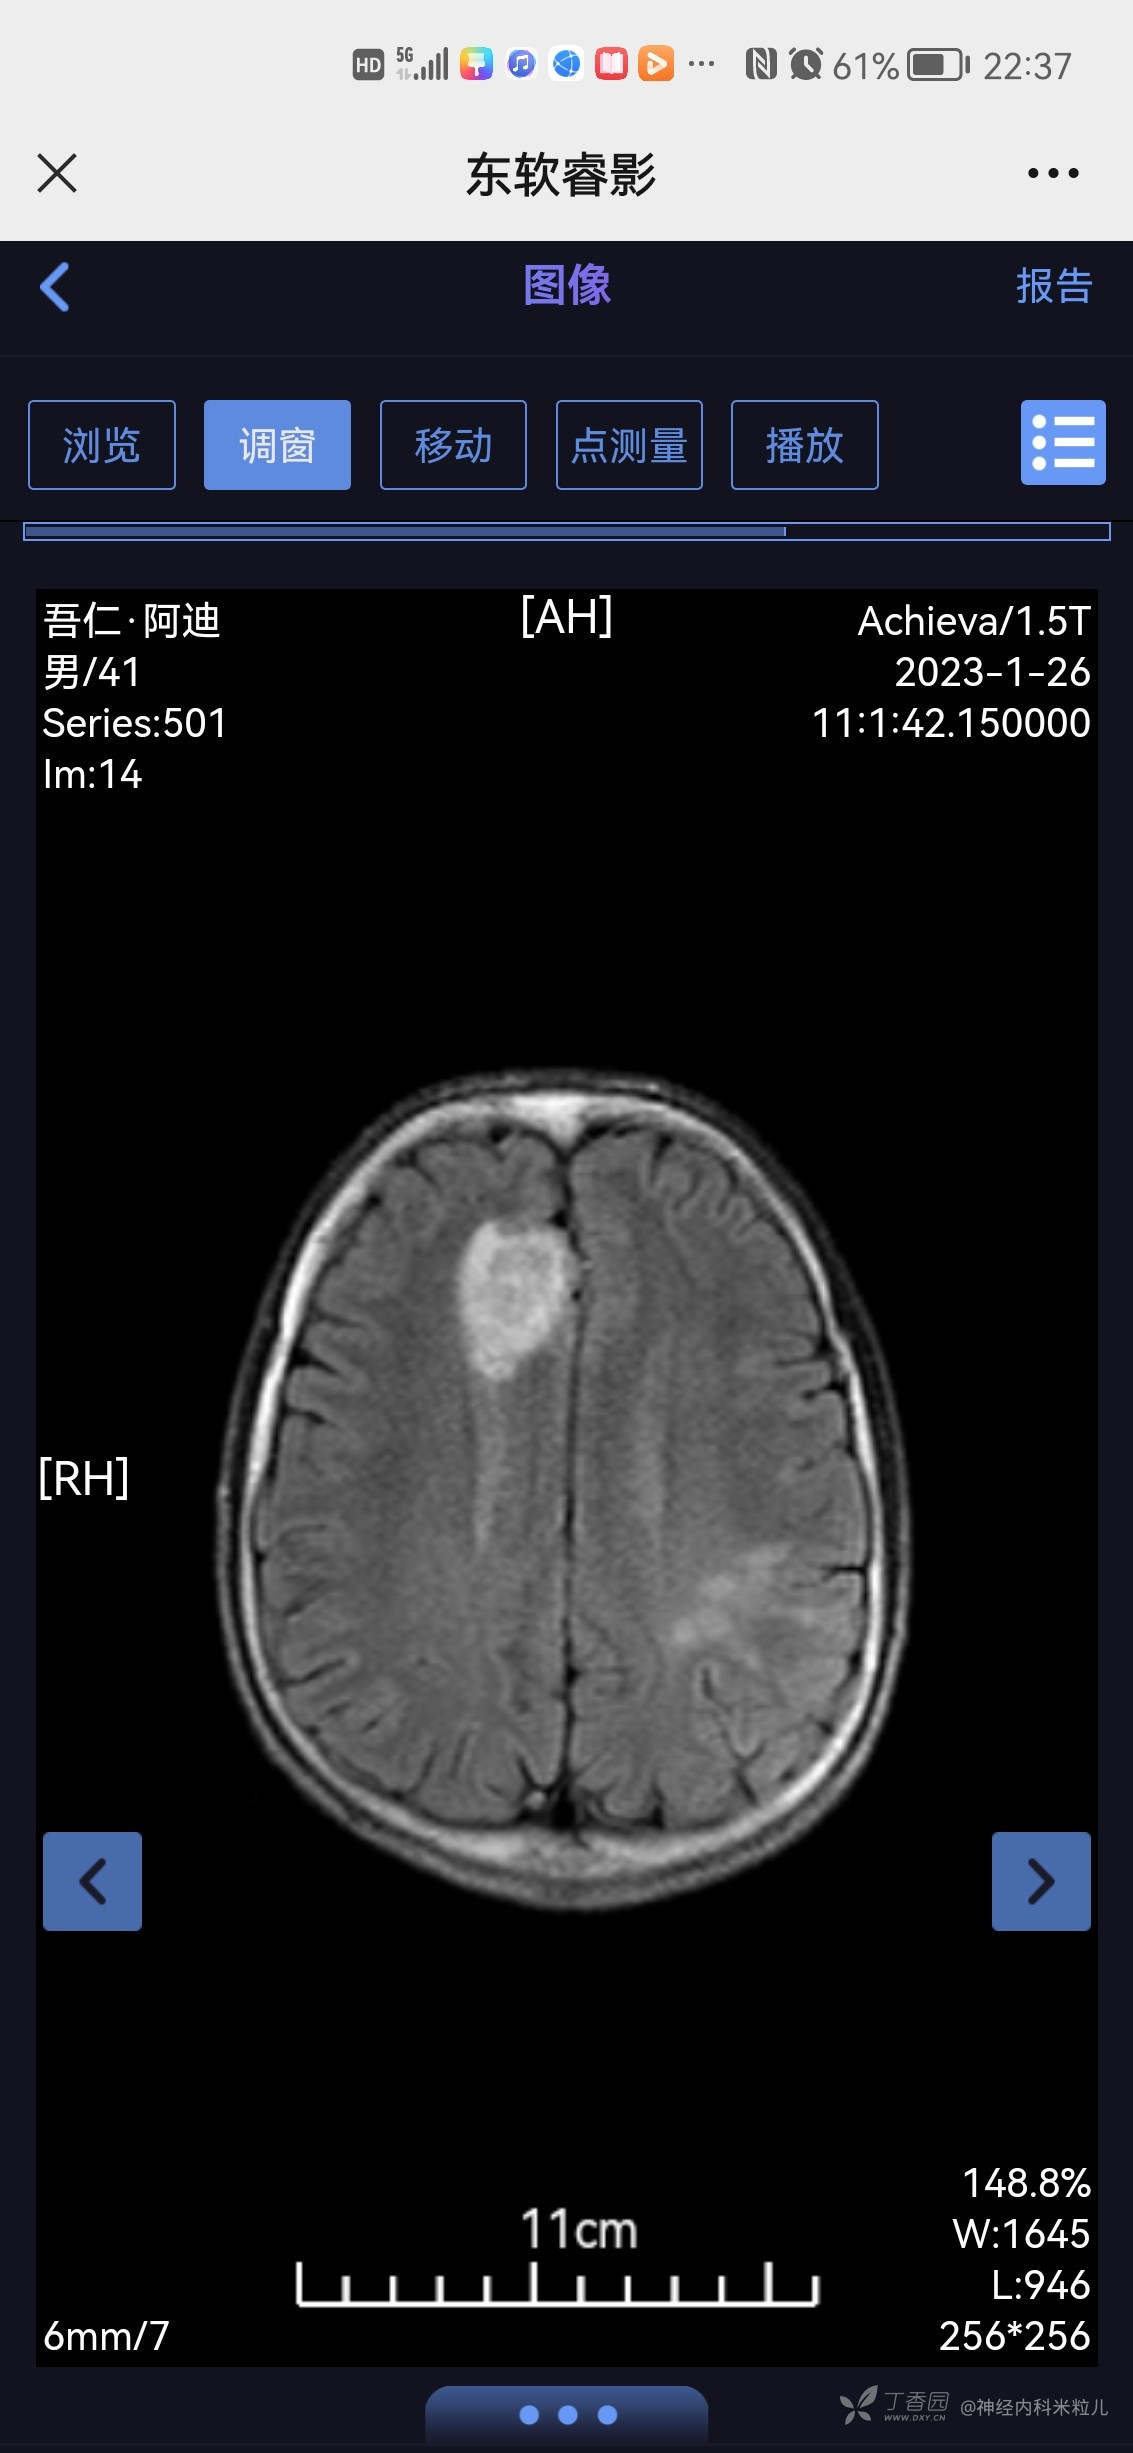

2023年1月18日我院头颅核磁提示:颅内多发异常信号,考虑:感染性病变,建议增强检查。}